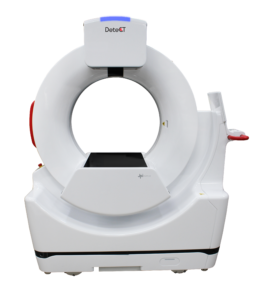

🔹 17″ x 17″ Live Video X-ray (30 FPS Full Fluoroscopy)

🔹 17″ x 17″ Radiography

Live Video X-ray

🔹30 FPS Full Flouroscopy (Without C-arm)

🔹17″ x 17″ Active Area

Go from Digital X-ray to Live Video X-ray mid-exam

without any adjustment to your patient

Powerful. Versatile.

Perform minimally-invasive diagnostic procedures and surgical interventions,

resulting in reduced patient recovery process

Diagnostic Applications

Surgical Applications

Tailored For Veterinarians

120 kVp Maximum Output Low Dose, High Frequency Generator for X-ray and Live Video X-ray

Industry-leading Image Quality and Diagnostic Results

Easy-to-use and Large Touchscreen Operating Console

User-friendly Interface

220V, 15A Power Requirements for Easy Installation

4-way Floating Table for Patient Positioning

Compact Unit with Wheels for Convenient Positioning and Easy Cleaning